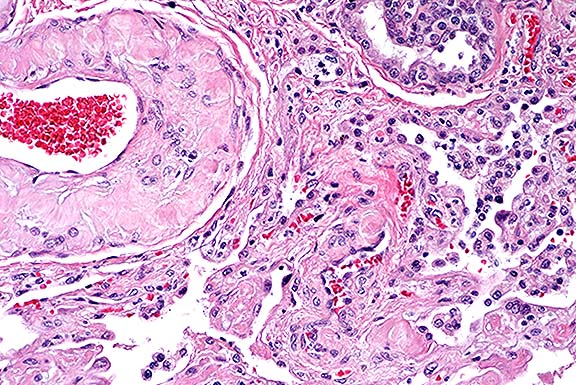

The kittens died of severe necrotizing pneumonia caused by

feline herpes- virus (FHV-1) infection. Significant microscopic

changes were confined to the lungs. Multifocally, bronchi and

bronchioles were necrotic and filled with fibrin, neutrophils

and cellular debris. There was multifocal patchy necrosis of alveoli,

with flooding of lumina with fibrin and cellular debris. In less

affected areas, alveolar septa were thickened by neutrophils,

fibrin and edema, with numerous microthrombi within alveolar capillaries.

Alveolar lumina contained small to moderate numbers of neutrophils

and fibrin. The stroma surrounding arteries and arterioles was

edematous and infiltrated by lymphocytes, macrophages and neutrophils.

The pleura was multifocally thickened by macrophages, neutrophils

and fibrin. Nuclei of remaining airway epithelial cells were occasionally

cleared, with margination of the chromatin and smudgy to discrete

eosinophilic inclusions. Indistinct, smudgy eosinophilic inclusions

were also found in scattered alveolar septal cells, surrounded

by a dark rim of marginated chromatin. Necrotizing bronchitis,

bronchiolitis and pneumonia with intranuclear eosinophilic viral

inclusion bodies are diagnostic of that agent. Transmission electron

microscopy on formalin fixed tissue was used to confirm the diagnosis;

typical 100-105 nm unenveloped icosahedral viral particles were

readily demonstrated in bronchial epithelial cell nuclei. In some

of the sections, typical type A Cowdry inclusions were difficult

to identify, due to the extensive necrosis of the bronchial/bronchiolar

epithelium.